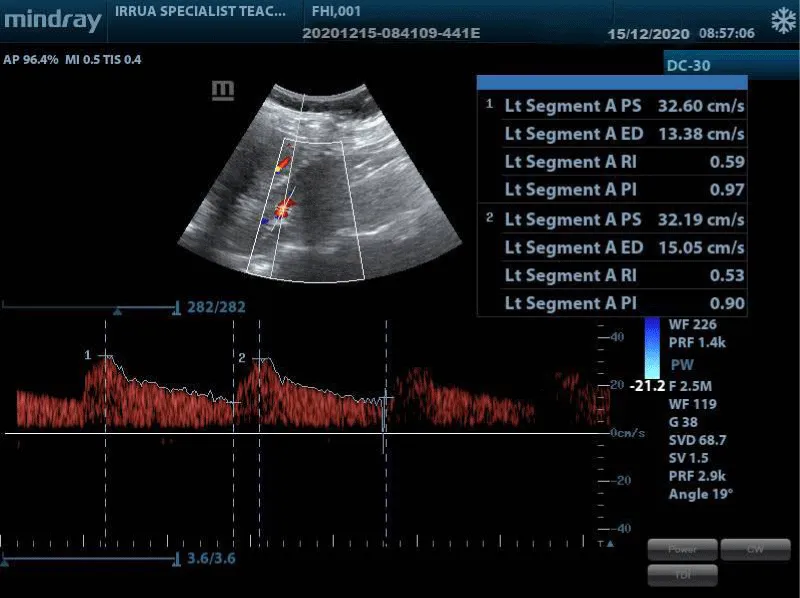

The US examination was performed using a curvilinear probe with a frequency of 3 – 5 MHz of a Mindray DC-30 (Shenzhen Mindray Bio-Medical Electronics Co., Ltd, China 2017) ultrasound machine with color and pulse Doppler facility. Each subject was made to lie supine on the couch with the abdomen adequately exposed from the upper abdomen to the symphysis pubis. The examination was performed with an empty bladder. Coupling gel was applied over the upper abdomen, using the liver on the right and spleen on the left as the acoustic windows. Longitudinal and transverse scans with Doppler interrogation of the kidneys were performed in the supine, supine oblique, and prone positions.

3. Resistive index: Triplex Doppler sonography was performed and spectral waveforms were obtained from the segmental renal arteries. Relevant measurements were taken from the upper, middle, and lower pole segmental arteries which were insonated using a 2 mm to 4 mm Doppler gate and an angle of insonation (theta) less than 20 degrees to enhance signal quality. The average of the three measurements was calculated and documented as the value for the kidney.

The values of the Peak Systolic Velocity (PSV), End Diastolic Velocity (EDV), Systolic Diastolic ratio (S/D) ratio, Resistivity Index (RI), and Pulsatility Index (PI) were recorded from the machine-generated values using auto-trace function.

Renal doppler parameters: Table 10 shows a comparison of renal Doppler velocimetry between HIV/AIDS and control subjects. In HIV/AIDS patients, the right renal PSV, EDV, SD, RI, and PI were greater than those for the left, except for the EDV, measuring 37.55 ± 8.03cm/s, 14.03 ± 8.50cm/s, 2.69 ± 0.32cm/s, 0.63 ± 0.04 and 1.10 ± 0.16 respectively versus 37.38 ± 12.40cm/s, 14.96 ± 5.33cm/s, 2.56 ± 0.34cm/s, 0.60 ± 0.05 and 1.02 ± 0.18 for the left renal values respectively. However, only the S/D, RI, and PI showed significant statistical differences between the right and left kidneys; p – values < 0.01, < 0.01 and < 0.01 respectively.

For the controls, the right renal PSV, EDV, S/D, RI, and PI in the controls measured 31.30 ± 6.72cm/s, 13.10 ± 3.18cm/s, 2.48 ± 0.39cm/s, 0.59 ± 0.06 and 0.97 ± 0.19 respectively. The left renal PSV, EDV, S/D, RI and PI in the controls measured 33.35 ± 9.57cm/s, 14.0 ± 3.89cm/s, 2.40 ± 0.33cm/s, 0.58 ± 0.05 and 0.94 ± 0.21 respectively. The right S/D, RI, and PI were greater than the left but only the S/D and RI were statistically significant; p - values 0.003 and 0.004 respectively. The left PSV and EDV were greater than the right and this difference was not statistically significant; p - values 0.09 and 0.06 respectively.

All the mean renal artery Doppler parameters (PSV, EDV, S/D, RI, and PI) of both kidneys were higher in the HIV/AIDS patients compared with the controls. There was a statistically significant difference in the right renal PSV, EDV, S/D, RI, and PI between the HIV/AIDS and control subjects; p = < 0.001, 0.038, < 0.001, < 0.001, and < 0.001. There was also a statistically significant difference in the left renal PSV, S/D, RI, and PI between HIV/AIDS and control subjects; p = 0.011, 0.001, <0.001, and 0.004. However, only the left renal EDV did not show any statistically significant difference; p –value 0.146 between the HIV/AIDS and control subjects Figure 6.

In this study, the normal control subjects had a mean RI of 0.59 ± 0.05 with an RI of 0.59 ± 0.06 and 0.58 ± 0.05 for the right and left kidneys respectively. This was similar to mean values of normal controls in studies by Atalabi, et al. [45] whose study reported an RI of 0.56 in 68 healthy adults at Ibadan, Nejad, et al. [46] in a study involving 30 normal control at Hashemi-Nejad Hospital, Tehran reported an RI of 0.59, while Sari, et al. [47] reported an RI of 0.56 in 50 healthy controls at KTU Farabi Hospital, Turkey. However, Ishimura, et al. [48] in a Japanese study reported a higher RI of 0.66 for 37 control subjects and also reported a positive correlation between age and RI values. The higher mean age of the Japanese study which was 58.5 ± 12.5years compared to the mean ages of 48.87 ± 8.47years and 50.1 ± 13.7years recorded by Atalabi, et al. and Nejad, et al. could be responsible for the higher RI values for the Japanese study. Also, factors such as small sample size and possible racial variation may be responsible for the different RI values.

The HIV/AIDS subjects recorded a mean RI of 0.62 ± 0.05 with an RI of 0.63 ± 0.04 and 0.60 ± 0.05 for the right and left kidneys respectively. The RI value was statistically higher in HIV/AIDS subjects than in control subjects; p = < 0.001 for both kidneys. These findings are similar to differences seen in studies between normal controls and subjects with chronic nephropathies including diabetics and hypertensive nephropathies [45-50]. In studies comparing healthy control subjects and patients with diabetic nephropathy – Nejad, et al [46] reported mean RI of 0.73 for diabetic patients and 0.59 for controls (p = < 0.001), Ishimura, et al. [48] reported RI of 0.76 compared with 0.66 for controls (p = < 0.001), Sari, et al. [47] reported RI value of 0.69 compared with 0.56 for controls (p = < 0.001), Dawha, et al. [49] also reported RI of 0.72 compared with 0.63 for controls (p = < 0.001). Also, in studies comparing hypertensives with control subjects Atalabi, et al. [45] reported an RI of 0.595 in hypertensives compared to 0.56 for controls. RI has a strong positive correlation with chronic renal disease associated with active tubule-interstitial disease, vasculitis, and vasculopathy but poor correlation with chronic renal disease limited to the glomeruli such as glomerulonephritis [48,51]. In HIV infection, there is direct infection of epithelial cells of the nephron, including the glomerulus, the tubules, and the collecting duct with associated podocyte proliferation and tubular dilatation, atrophy and flattening of tubular epithelia cells, interstitial edema and inflammation and often accompany interstitial fibrosis which are all features of classic HIVAN [52,53]. Furthermore, renal parenchyma disease results in loss of diastolic flow indicating an increase in vascular resistance or increase in parenchymal pressure within the kidney resulting in an increased RI [26]. These tubulo-interstitial damages may be responsible for the increased vascular resistance resulting in the statistical difference of the renal Doppler RI between the HIV/AIDS and control subjects.